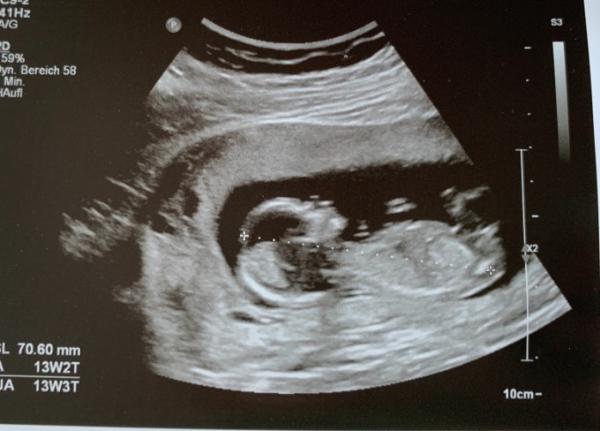

Antwort auf Beitrag von Würmchen032020

Bild 2 Vielleicht kennt sich jemand aus... ich leider garnicht.

Ich bin echt kein Experte, aber ich glaube ich erkenne einen Winkel mehr als 30 Grad, also tippe ich junge :)